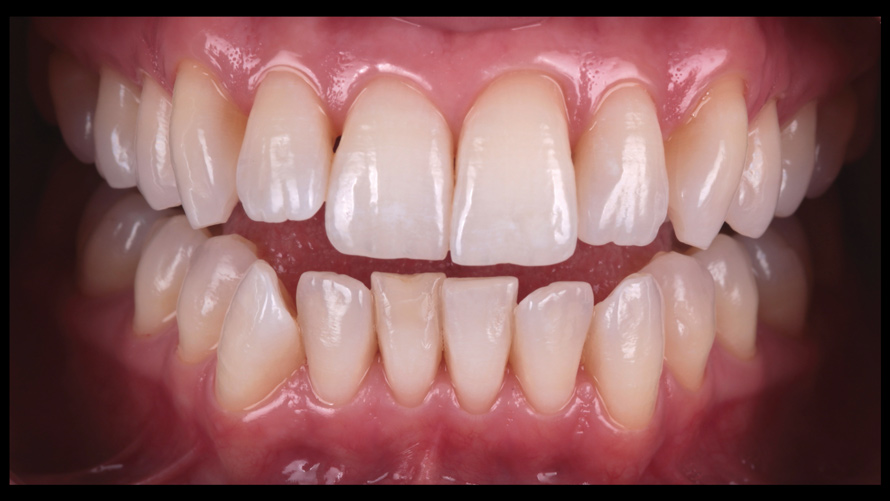

(9.) Preoperative esthetic case documentation using a smartphone and an EALS device.

Figure 9

(10.) Preoperative esthetic case documentation using a smartphone and an EALS device.

Figure 10

(11.) Preoperative esthetic case documentation using a smartphone and an EALS device.

Figure 11